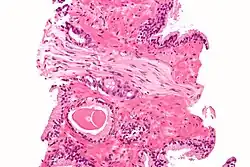

- G1–4: Grading, Angabe, wie differenziert das Tumorgewebe ist. G1 = gut differenziert (das Tumorgewebe ist dem Ursprungsgewebe noch relativ ähnlich), G4 = undifferenziert (das Ursprungsgewebe ist nur noch über ultrastrukturelle oder immunhistochemische Untersuchungsmethoden differenzierbar).